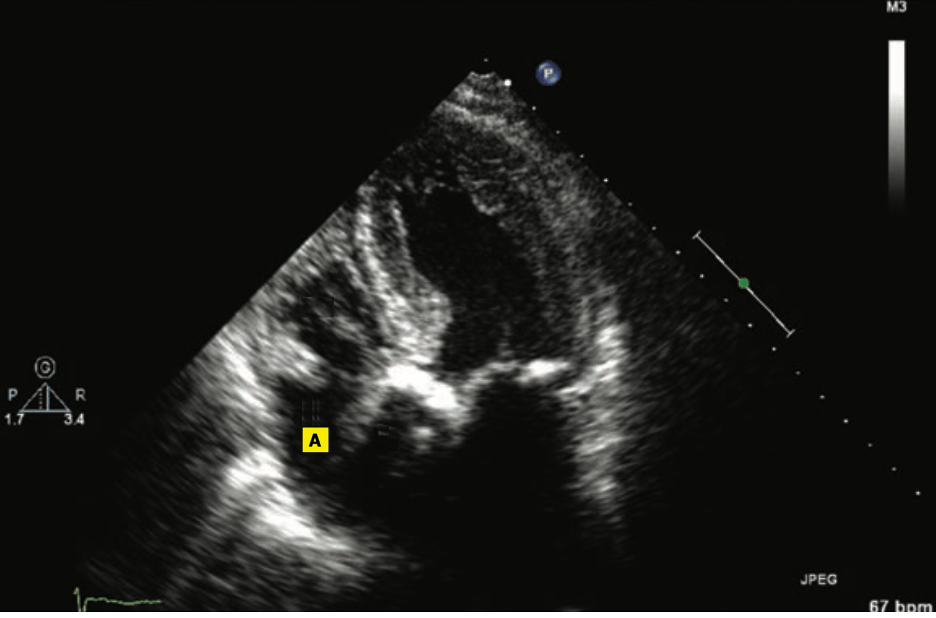

In a 5-chamber view of the heart, this is the structure marked “A”

What is the right atrium?